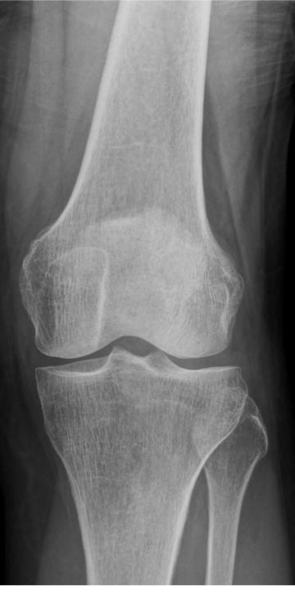

初診レントゲン(X線)

初期では、痛みが強くてもレントゲンで明らかな異常が写らないことがあります。